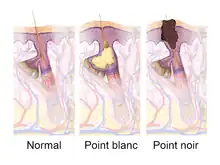

les glandes sébacées jouent un rôle dans certains problèmes cutanés comme l'acné, la dermatite séborrhéique ou encore la kératose pilaire. Dans les pores cutanés, le sébum et les débris de kératine peuvent s'impacter[pas clair] et créer un bouchon appelé comédon.

L'acné est un phénomène courant, particulièrement fréquent pendant la puberté chez les adolescents, et est considérée comme étant liée à une production accrue de sébum due à des facteurs hormonaux. La production accrue de sébum peut entraîner un blocage du conduit excréteur de la glande sébacée, provoquant un comédon (communément appelé point noir ou point blanc), qui peut entraîner à son tour une infection, notamment par la bactérie Cutibacterium acnes, et provoquer les lésions caractéristiques. Les comédons apparaissent généralement dans les zones où il y a plus de glandes sébacées, en particulier le visage, les épaules, le haut de la poitrine et le dos. Ils peuvent être noirs ou blancs selon que l'annexe pilo-sébacée entière, ou seulement le conduit sébacé, est bloqué[27].